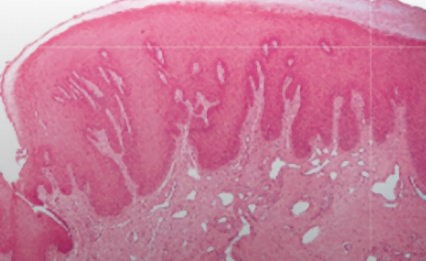

| Verruciform xanthoma (非 HPV) | Leasion 旁,異常免疫反應 | 口腔 > 皮膚 > 性器 | 油脂撐起 epi. 形成 Verruciform。非 Metabolic   |

|||

|

||||||

- xanthoma

- 吃了油脂的 Macrophage 細胞,CD63+, CD68+, CD163+ IHC8+,diastase-PAS染色+

diastase-PAS

- diastase: 澱粉酶

- PAS: Periodic Acid-Schiff stain

- 過碘酸氧化 OH 成 =O,Schiff 染